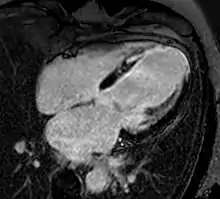

![]() An example of CMR movies in different orientations of a cardiac tumor - in this case, an atrial myxoma.[1] | |